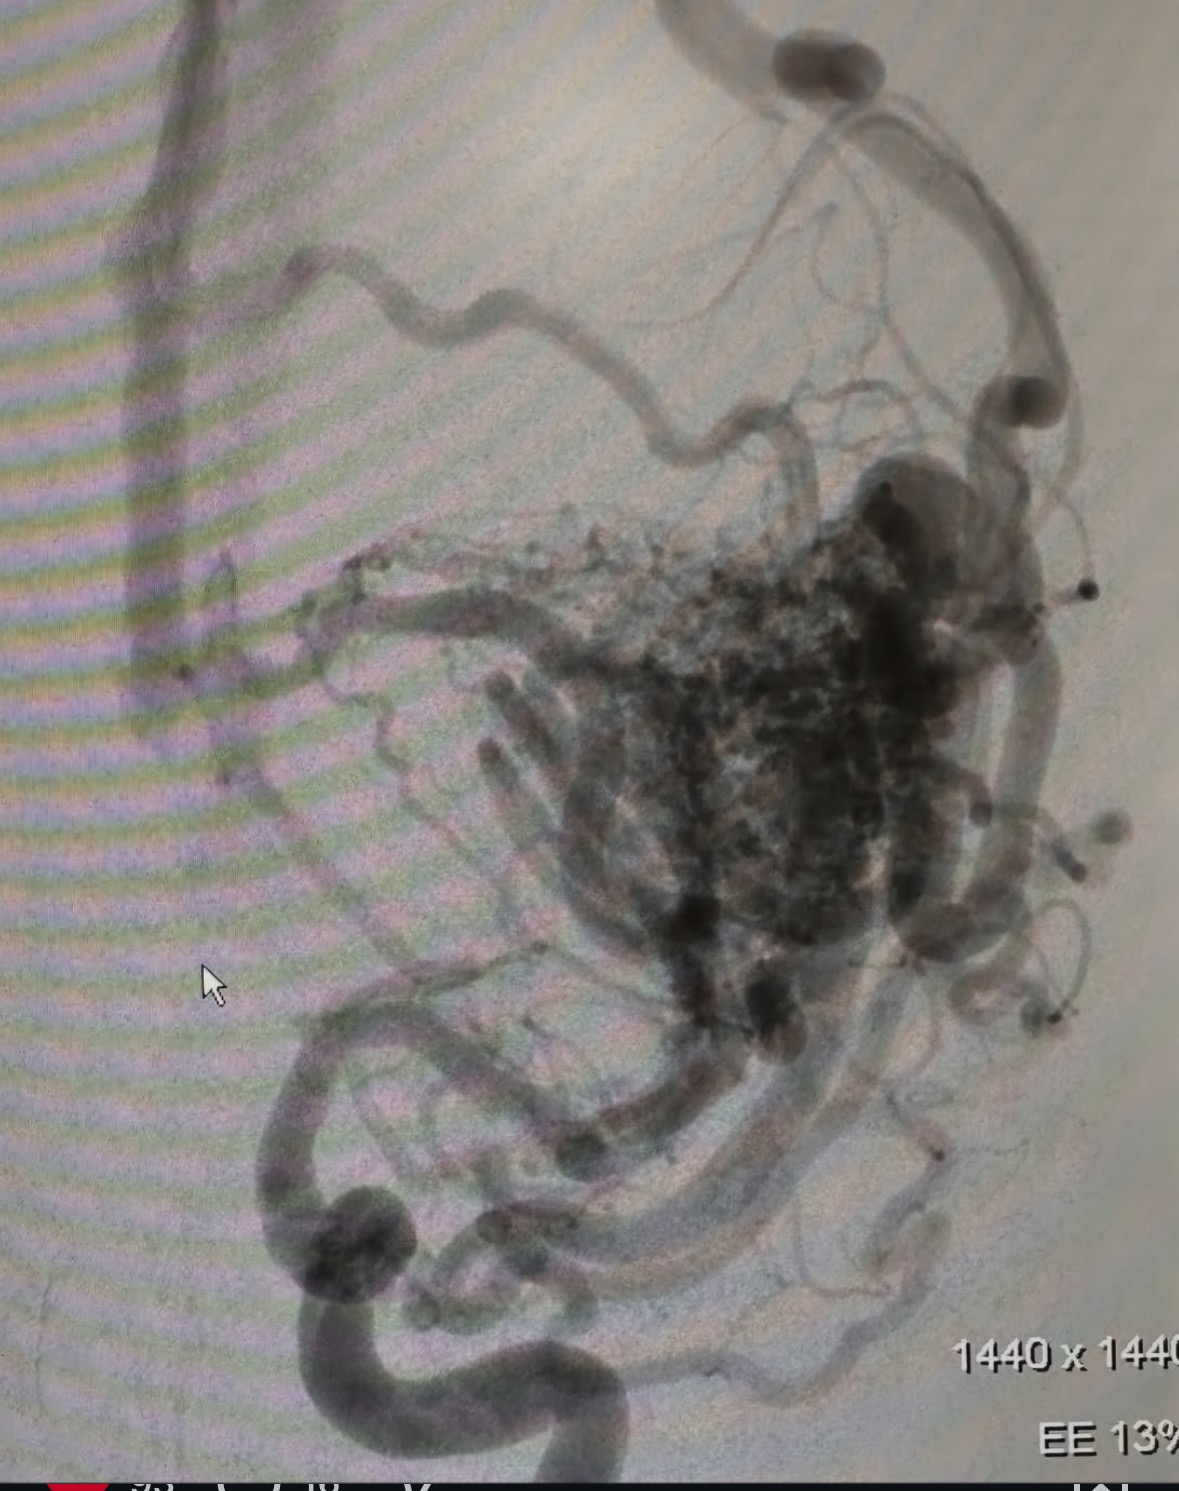

On April 4, Brecken experienced her first seizure, while on shift at the fire station at her job in Eagle River Fire District. She was quickly transferred to the hospital in Vail and cared for. Breck has an AVM (Arteriovenous Malformation) which is a tangle of blood vessels that creates irregular connections between arteries and veins in the brain that can cause seizures. Breck's AVM is on her left frontal lobe, which is where the language center is located. So traditional brain surgery is high risk, with potential to lose speech and function on the right side of her body.